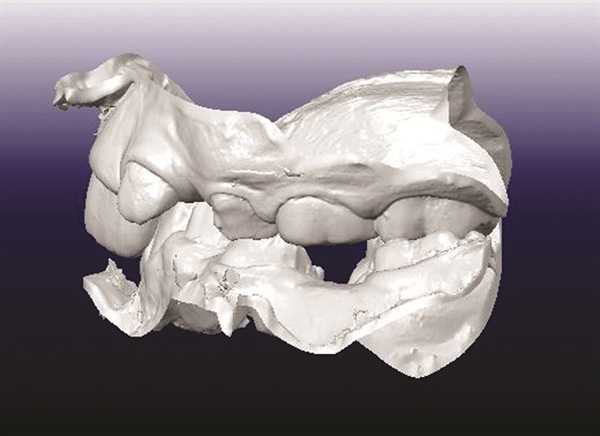

A 12-year-old male presented with severe Class II, deep bite, and significant crowding. The original poster was torn between two conflicting clinical pictures. Half the diagnostic findings pointed toward extraction: second molars impacted in the ramus, a blocked lower left canine, blocked maxillary canines, and a nearly full-step Class II relationship. The other half suggested non-extraction with vertical control to avoid deepening the bite further. The concern was that by the time crowding was resolved and the deep bite corrected, the incisors would be too flared for effective Class II correction without further proclination. The question posed to the forum was whether immediate upper first premolar and lower second premolar extractions were the best route forward (Figs. 1–11).

Fig. 2